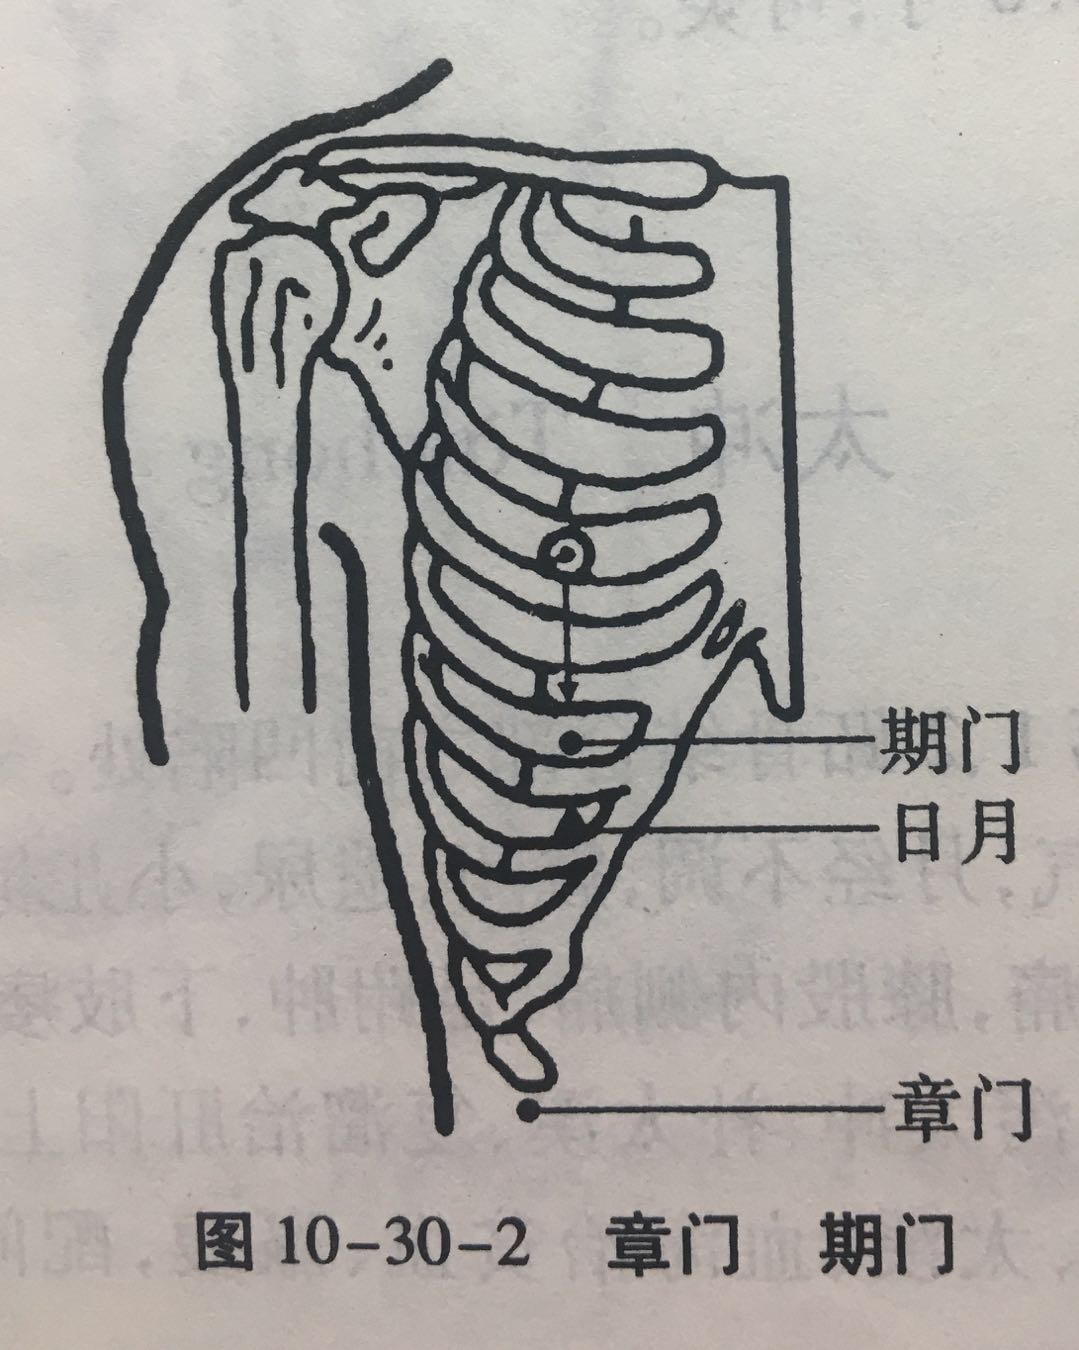

章门

【定位】 在侧腹部,当第 11 肋游离端的下方(图 10-30-2)。

【主治】 腹痛,腹胀,肠鸣,泄泻,呕吐,神疲肢倦,黄疸,痞块,小儿疳积,腰脊痛。

【配伍】 配足三里治荨麻疹、组织胺过敏症,配天枢、脾俞、中脘、足三里治肝脾不和之腹胀、痞块、胁痛,泄泻,消瘦,配肾俞、肝俞、水道、京门、阴陵泉、三阴交、阳谷、气海治肝硬化腹水、肾炎。

【刺灸法】 斜刺 0.5 ~ 0.8 寸;可灸。

【附注】 脾的募穴,八会穴之脏会。

期门

【定位】 在胸部,当乳头直下,第 6 肋间隙,前正中线旁开 4 寸(图 10-30-2)。

【主治】 胸胁胀满疼痛,呕吐,呃逆,吞酸,腹胀,泄泻,饥不欲食,胸中热,咳喘,奔豚,疟疾,伤寒热入血室。

【配伍】 配大敦治疝气,配肝俞、公孙、中脘、太冲、内关治肝胆疾患、胆囊炎、胆结石及肝气郁结之胁痛、食少、乳少、胃痛、呕吐、呃逆、食不化、泄泻等。

【刺灸法】 斜刺 0.5 ~ 0.8 寸;可灸。

【附注】 肝的募穴。